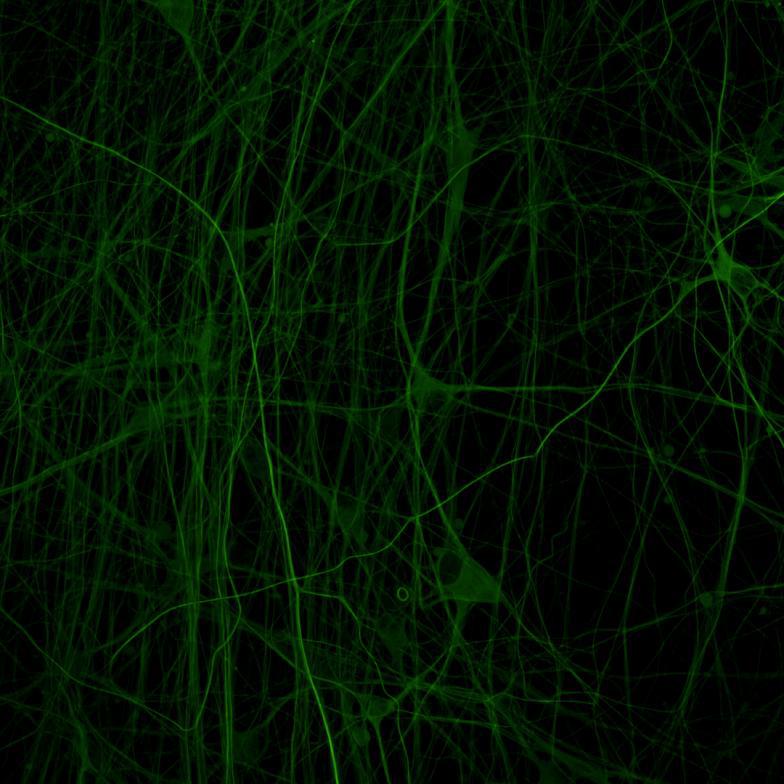

• Wildtype neurons were transduced with a lentivirus to express a full-length 4R tau isoform with a familial frontotemporal dementia P301L mutation labelled with EGFP

• Neurons were then exposed to recombinant tau preformed fibrils (PFFs) and imaged

• Increasing over time, PFF exposure induced areas of bright EGFP-positive aggregates of full-length tau, and aggregation of the K18 fragment FRET pair as seen by positive normalised FRET (NFRET) signal